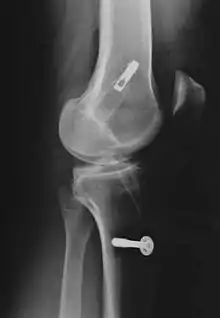

Grafts are inserted through a tunnel that is drilled through the shin bone (tibia) and thigh bone (femur). The graft is then pulled through the tunnel and fixated with screws. The two bright objects in this X-ray are screws in the thigh bone (above) and shin bone (below).